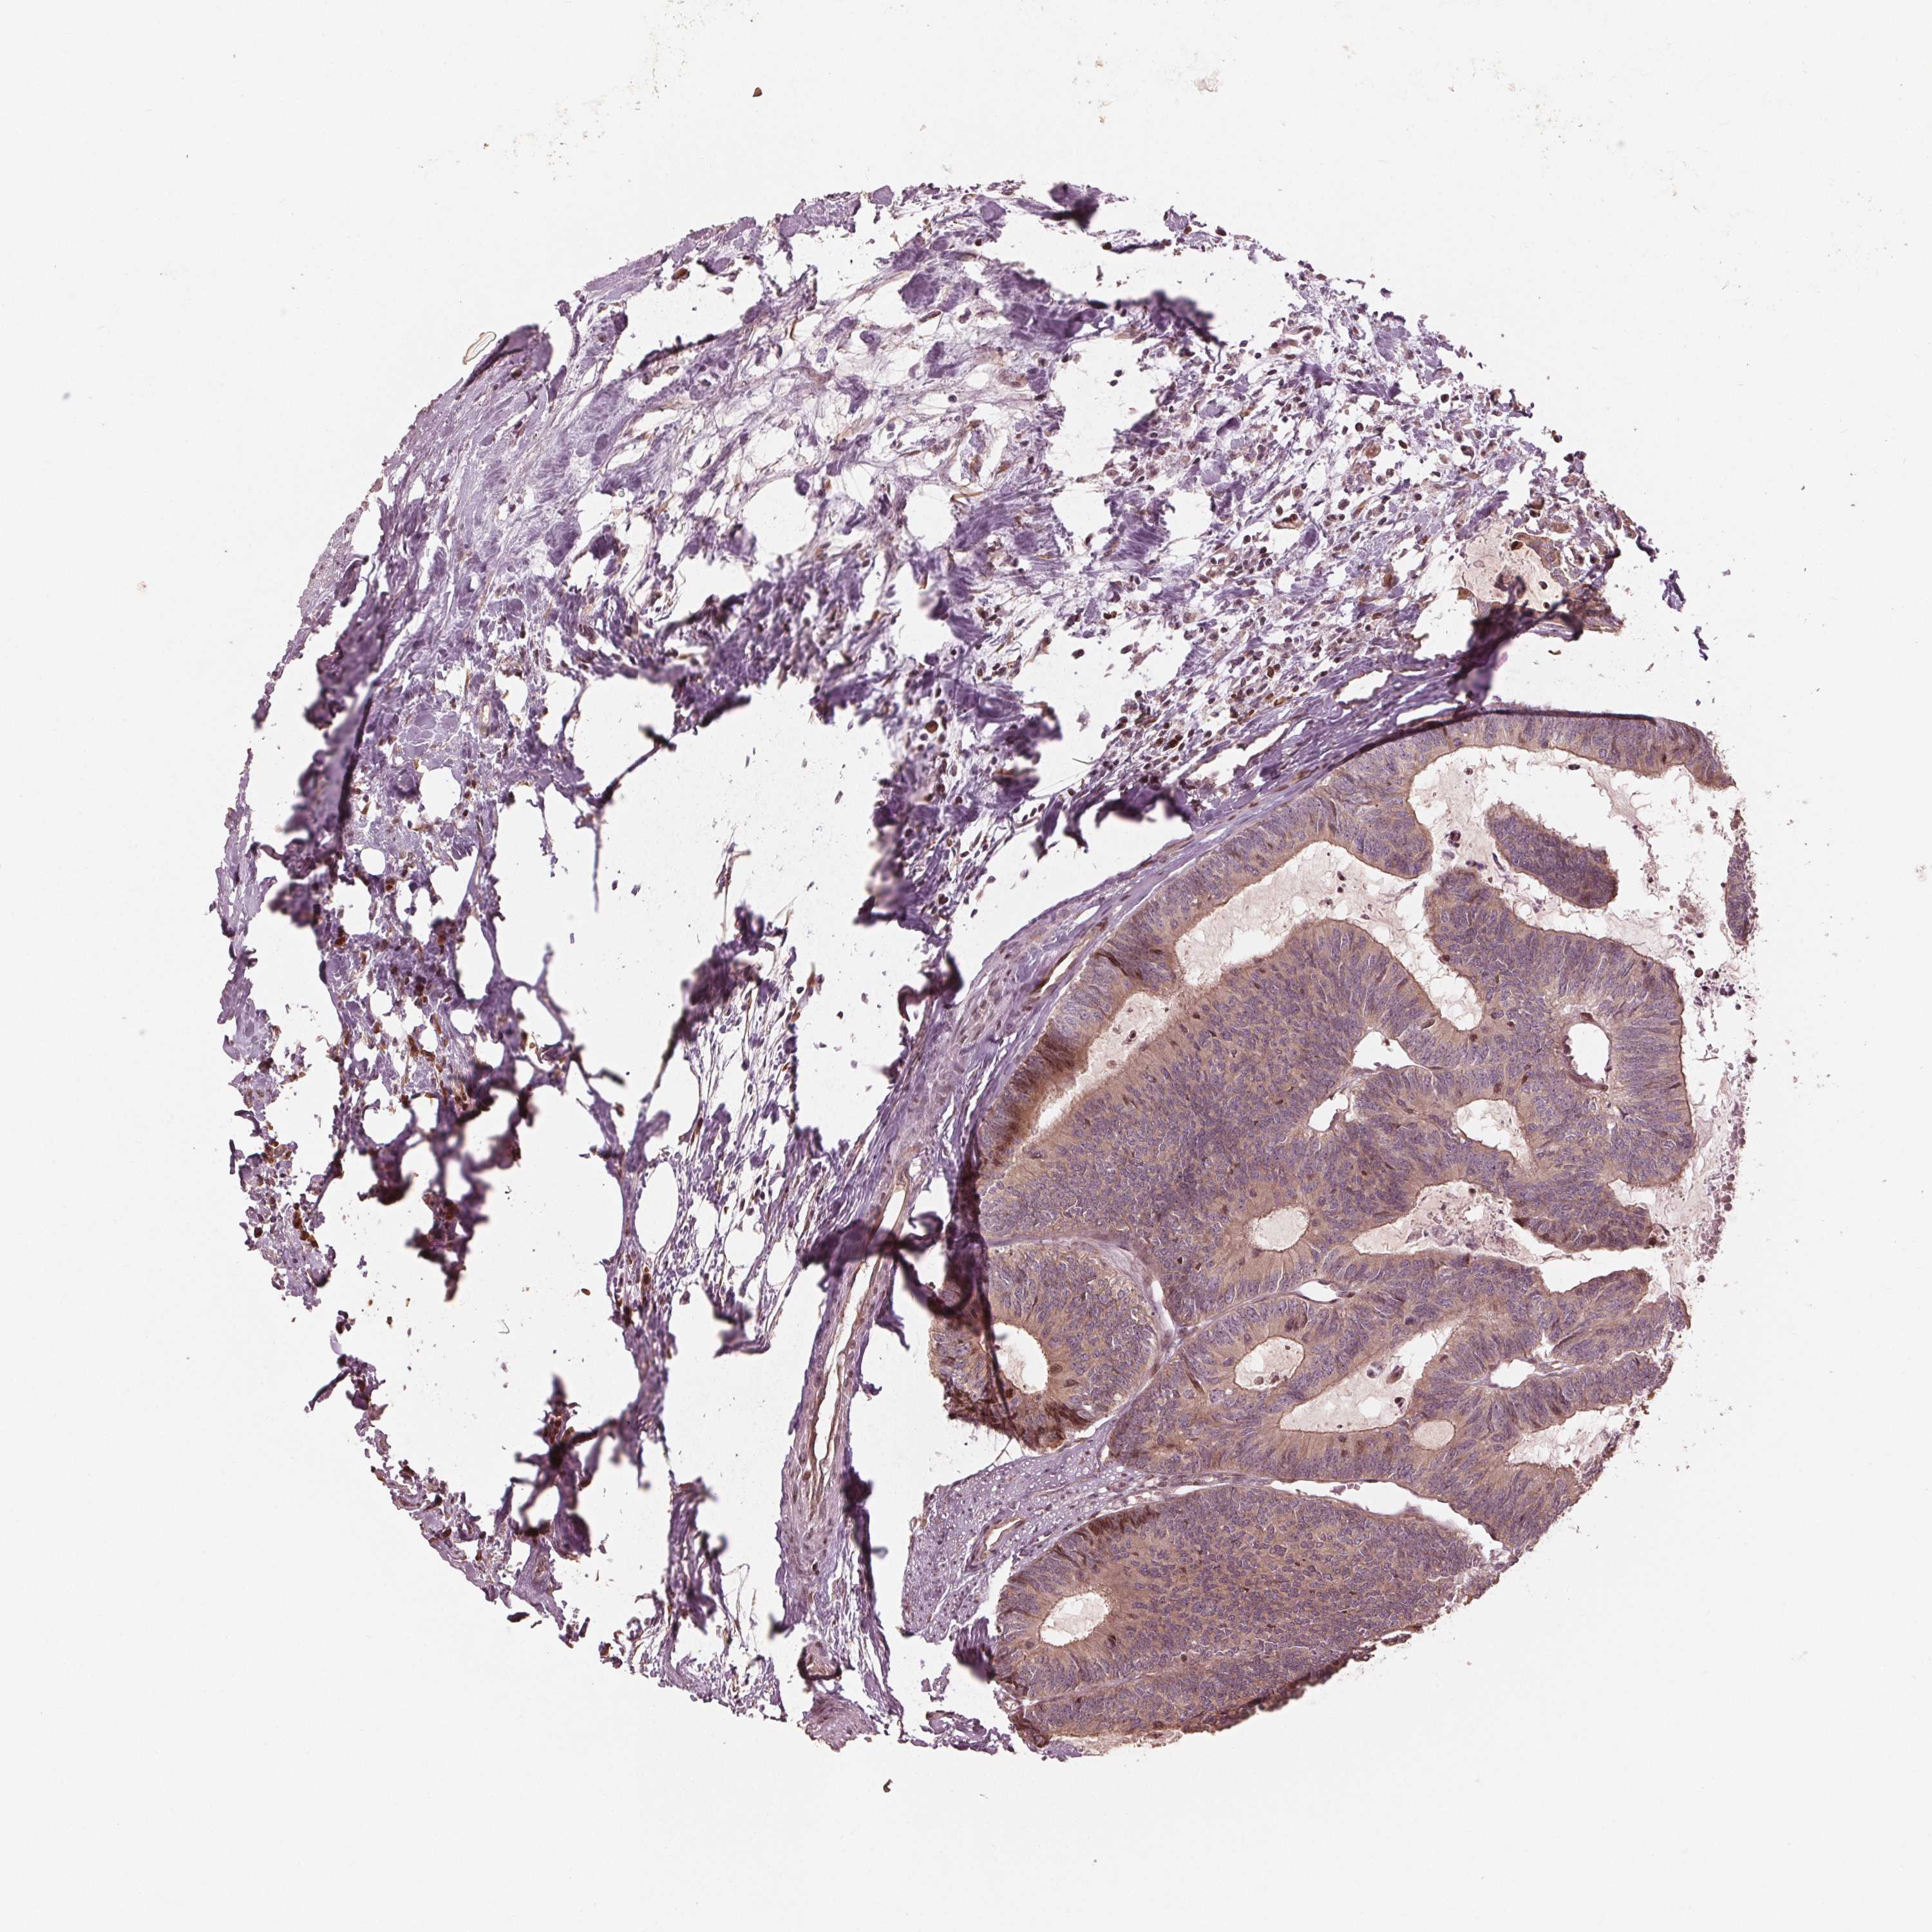

CANCER COLORECTAL CANCER Show tissue menu

Colorectal cancer